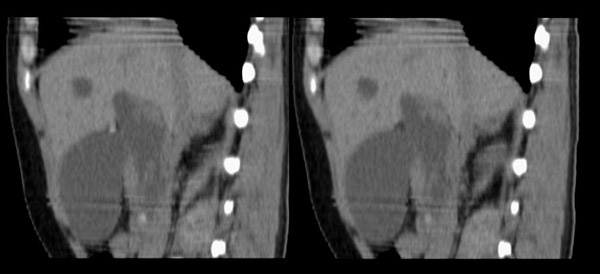

胆总管矢状及冠状重建:

胆总管结石\\肝左叶肝内胆管结石,胆道蛔虫钙化伴胆系梗阻\\胆囊积水.

胆总管结石并肝内外胆管扩张、肝左叶肝内胆管结石、胆囊大。

行胆囊切除术及胆总管探查术:探查见肝脏大小正常,肝缘稍钝,肝表面光整,胆囊大小12*3*3cm3,壁水肿增厚约0。5cm,张力稍高,胆囊与大网膜呈纤维粘连;胆总管宽约2cm,壁明显增厚,触摸胆总管,隐约可触及一条状物,于胆总管做一长约1、5cm的纵行切口,用取石钳在胆总管内取出一条长约16cm长黑色的长条状物,较脆易折断,宽约0、6cm,证实为蛔虫尸体。用探子往下探,未发现下端结石最后诊断:胆道蛔虫症继发胆系梗阻性扩张。